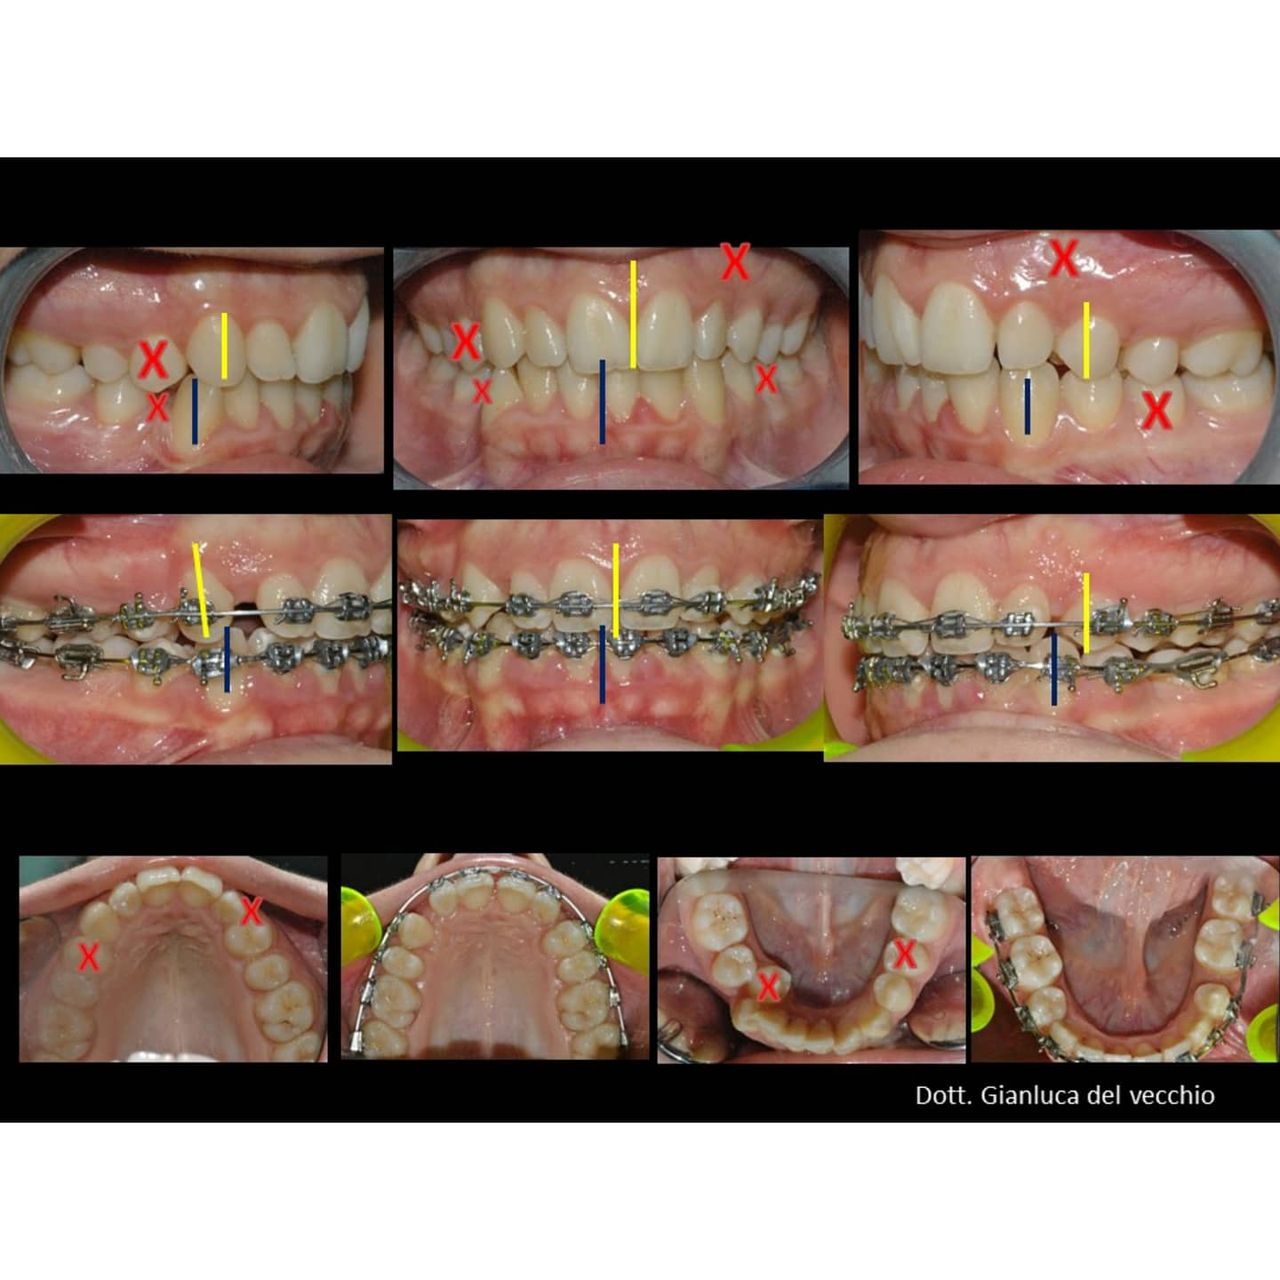

Il dottor Gianluca del Vecchio si occupa esclusivamente di ortognatodonzia, grazie anche alla collaborazione multidisciplinare di una équipe davvero entusiasmante e all’utilizzo di strumenti diagnostici e terapeutici all’avanguardia in ortognatodonzia. Particolare è la sua capacità di condurre i giovani pazienti ad affrontare, nella massima sicurezza emotiva e clinica, qualsiasi eventuale condizione di dolore derivante, ad esempio, da carie o da altre patologie, ma soprattutto di risolvere tutte quelle condizioni di “denti storti”, così spesso causa di disagio psicologico o di fenomeni deprecabili, quale il bullismo.

Queste le ragioni che consentono di trattare le malocclusioni, sia dei bambini che degli adulti, con protocolli scientificamente validati come i più veloci, affidabili e confortevoli.